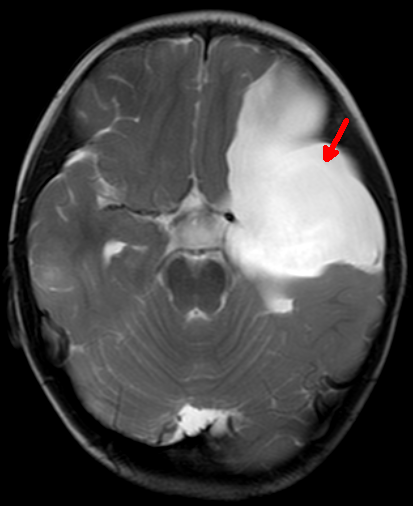

2岁的浩浩(化名)是个可爱男宝宝。一个月前家人发现他间断恶心、呕吐,在当地医院查了个头部的CT,结果显示浩浩左侧接近一半的脑子被一个巨大“水球”所占据,医学上叫做“中颅窝蛛网膜囊肿”。由于孩子太小,家人很是谨慎,经过多方打听了解到郑州大学五附院有神经内镜治疗颅内蛛网膜囊肿技术,于是转入神经外科三病区就诊。浩浩的病情得到了付旭东主任和麻醉科胡强夫主任及其团队的高度重视,为其制定了周密的手术方案,同样要把“死水”变成“活水”。在兄弟科室的通力合作下手术过程顺利,术后浩浩的症状明显改善,家人悬着的一颗心也终于落了地。同样由于神经内镜创伤小的优点,浩浩很快顺利康复出院。

左中颅窝巨大蛛网膜囊肿,占据了近一半脑子

术后11天复查MRI囊肿明显缩小,脑组织回弹